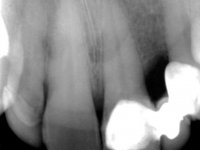

Fifty year old male patient, non-smoker. Carries a Maryland Bridge replacing tooth 2.2. "Maryland wings" are metallic and the dental surfaces in contact with them are infiltrated. Tooth 2.1 had a feldspathic ceramic veneer covering the vestibular surface. Tooth 1.2 presented a feldspathic ceramic veneer with exposed cervical margin. The edentulous space corresponding to tooth 2.2 is narrow and tall. Patient presents an open anterior bite, good oral hygiene and reasonable periodontal health.